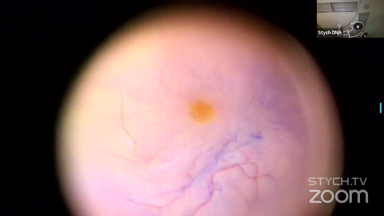

The Surgical Streaming Society (SSS) is a pioneering platform dedicated to advancing surgical education through live streaming. Our mission is to create an interactive learning environment where surgeons can share and collaborate on various surgical techniques and advancements. The SSS site is open to Registered Viewers who can access and view our member and partner video highlight pearls.

Viewer Discretion Advised: The videos may contain graphic images of surgical procedures that could be disturbing. Viewer discretion is advised. The site is intended for users who are 18 years or older, and no viewers under 18 years of age are allowed unless the use of the site is part of a class within an institution of secondary education and the viewing is supervised by an adult education professional.